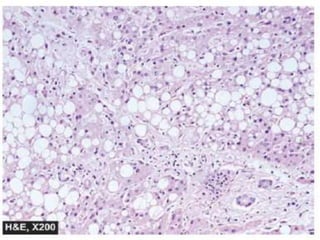

Microscopically, characteristic feature is the presence

of numerous lipid vacuoles in the cytoplasm of

hepatocytes.

Fat in H & E stained section prepared by paraffin embedding technique

appear non-staining vacuoles because it is dissolved in alcohol.

i) The vacuoles are initially small and are present around

the nucleus (microvesicular).

ii) But with progression of the process, the vacuoles

become larger pushing the nucleus to the periphery of

the cells (macrovesicular).

iii) At times, the hepatocytes laden with large lipid

vacuoles may rupture and lipid vacuoles coalesce to form

fatty cysts.

Fatty liver. Many of the hepatocytes are distended with large fat vacuoles

pushing the nuclei to the periphery (macrovesicles), while others show multiple small vacuoles

in the cytoplasm (microvesicles).